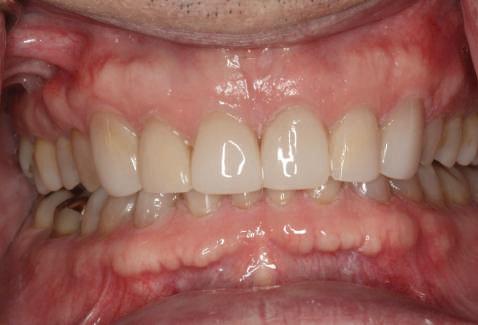

Atitudine: Până la dobândirea vindecării totale a ţesuturilor şi a implanturilor secundare s-au utilizat bonturi standard de titan. Fig. 18 prezintă bonturile individualizate maxilare şi mandibulare aplicate iar fig. 19 un prim-plan al cadranelor de partea dreaptă a pacientului, afişând finalizarea cazului la 15 luni după începerea tratamentului iniţial. Recesiile se pot obiectiva corespunzător 1.4. şi 1.3. În acest caz, s-a încercat minimizarea susceptibilităţii la recesie prin implicarea bonturilor temporare standard fixate cu şurub în cursul fazelor de vindecare pe toată durata etapelor iniţiale ale tratamentului.

În pofida acestor eforturi, totuşi, recesia a apărut în anumite regiuni unde implanturile erau plasate vestibular. Ulterior, s-a încercat grefarea ţesutui moale din jurul locaţiilor cu recesie, dar fără succes.

Cazul (6)

Submergenţa radiculară

Acest pacient s-a prezentat cu o punte 1.3.-2.3. compromisă.

Pentru a păstra limitele restaurării fixe pe toată durata tratamentului, s-au inserat în primă etapă implanturi corespunzător 1.3. şi 2.3. După integrarea acestora, s-au aplicat bonturi individualizate, iar restaurarea provizorie s-a rebazat pentru suplimentarea suportului.

Implanturile şi bonturile ulterioare aferente s-au putut poziţiona în poziţiile 1.2. şi 2.1. Incisivul 1.1. a beneficiat de tratament endodontic electiv pentru a fi redus şi în cele din urmă, după inserarea bonturilor pe implanturile 1.2. şi 2.1., a fost scufundat (fig. 20, 21).

Atitudine: În fig. 21, este evident că, după submersiunea radiculară, nu se

obiectivează recesie în jurul bonturilor 1.2. şi 2.1. De notat osul excelent vestibular în dreptul tuturor implanturilor, fără recesie în jurul 1.3. şi 2.3. (fig. 22) care au fost inserate cu 8 luni înainte de 1.2. şi 2.1. Perioada scursă între scufundarea rădăcinii (fig. 20) şi inserarea punţii finale (fig. 22) a fost de 7 luni (fig. 23).

Cazul (5):

Bonturi conice utilizate ca bonturi temporare

Figurile

16, 17. Implanturile din prima etapă încărcate cu bonturi conice şi, în unele cazuri, omologii angulaţi.

18. Bonturile individualizate inserate.

19. Rezultat final la 15 luni după începerea tratamentului iniţial.

şi va induce resorbţie osoasă şi migraţia apicală a ţesutului (Saadoun & Touati). Dacă implantul nu este plasat mai palatinal şi la 3-4mm apical de marginea gingivală liberă pentru a asigura profilul de emergenţă adecvat, rezultatul estetic este compromis (Chu et al). Un studiu de 2 ani a demonstrat că implanturile poziţionate anterior au demonstrat o recesie uşor mai accentuată, decât implanturile posterioare (Bengazi et al). Plasarea vestibulară a implanturilor se poate vizualiza clar în cazul 5 (fig. 17) cu bonturile de vindecare în poziţie.